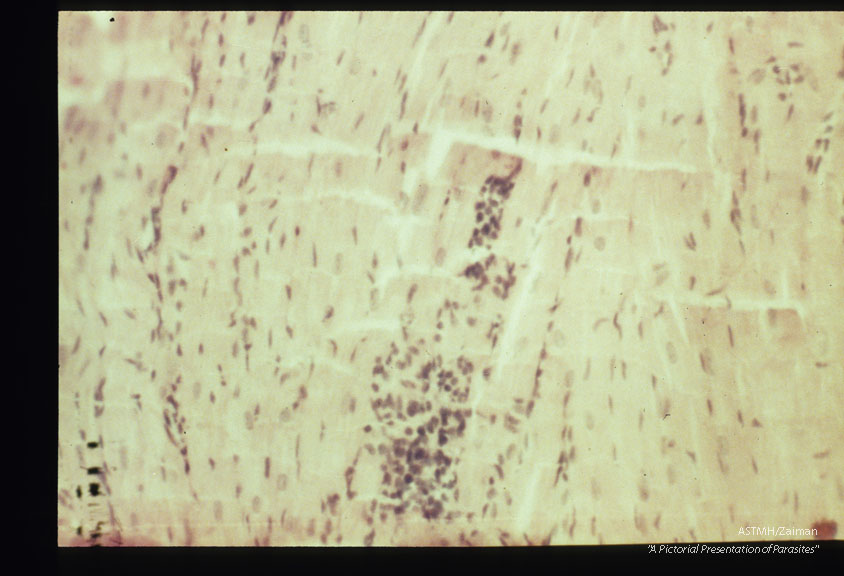

Focal myocardial lesions at low and high powers. Experimental trichinous myocarditis in rats.

Trichinella spiralis

Description: Focal myocardial lesions at low and high powers. Experimental trichinous myocarditis in rats.